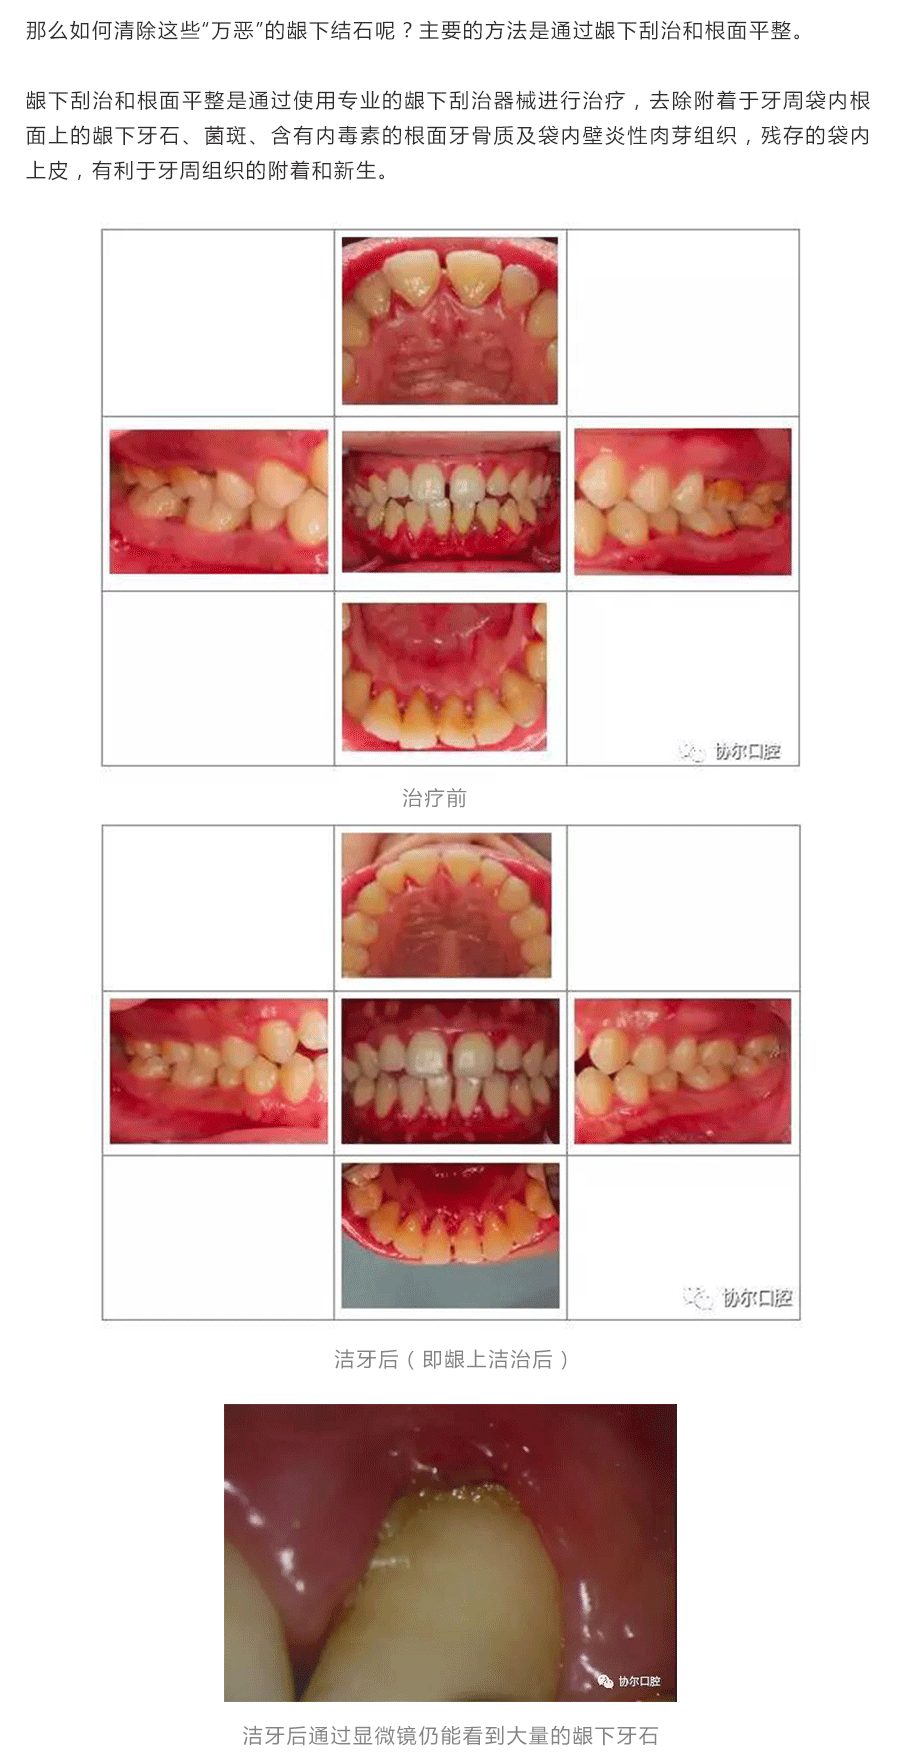

牙周治疗